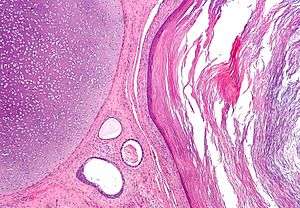

Micrograph of a teratoma, a tumour that characteristically has tissue from all three germ layers. The image shows tissue derived from the mesoderm (immature cartilage - left-upper corner of image), endoderm (gastrointestinal glands - center-bottom of image) and ectoderm (epidermis - right of image). H&E stain.